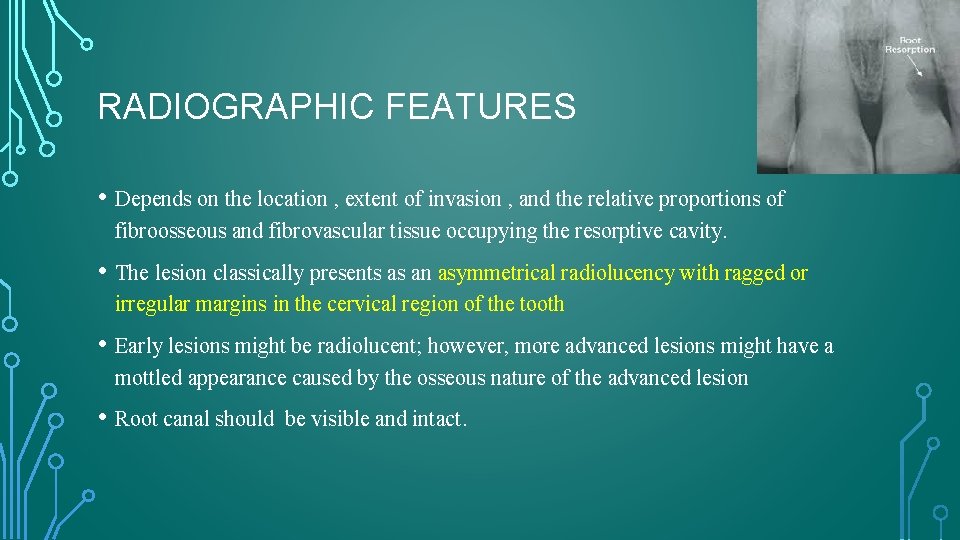

RADIOGRAPHIC FEATURES • Depends on the location , extent of invasion , and the relative proportions of fibroosseous and fibrovascular tissue occupying the resorptive cavity. • The lesion classically presents as an asymmetrical radiolucency with ragged or irregular margins in the cervical region of the tooth • Early lesions might be radiolucent; however, more advanced lesions might have a mottled appearance caused by the osseous nature of the advanced lesion • Root canal should be visible and intact.